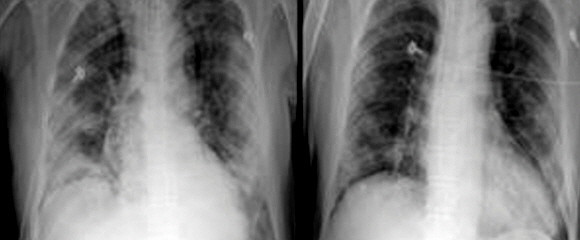

코로나19 혈장치료 효과…"중증 폐렴 환자 2명 모두 완치"